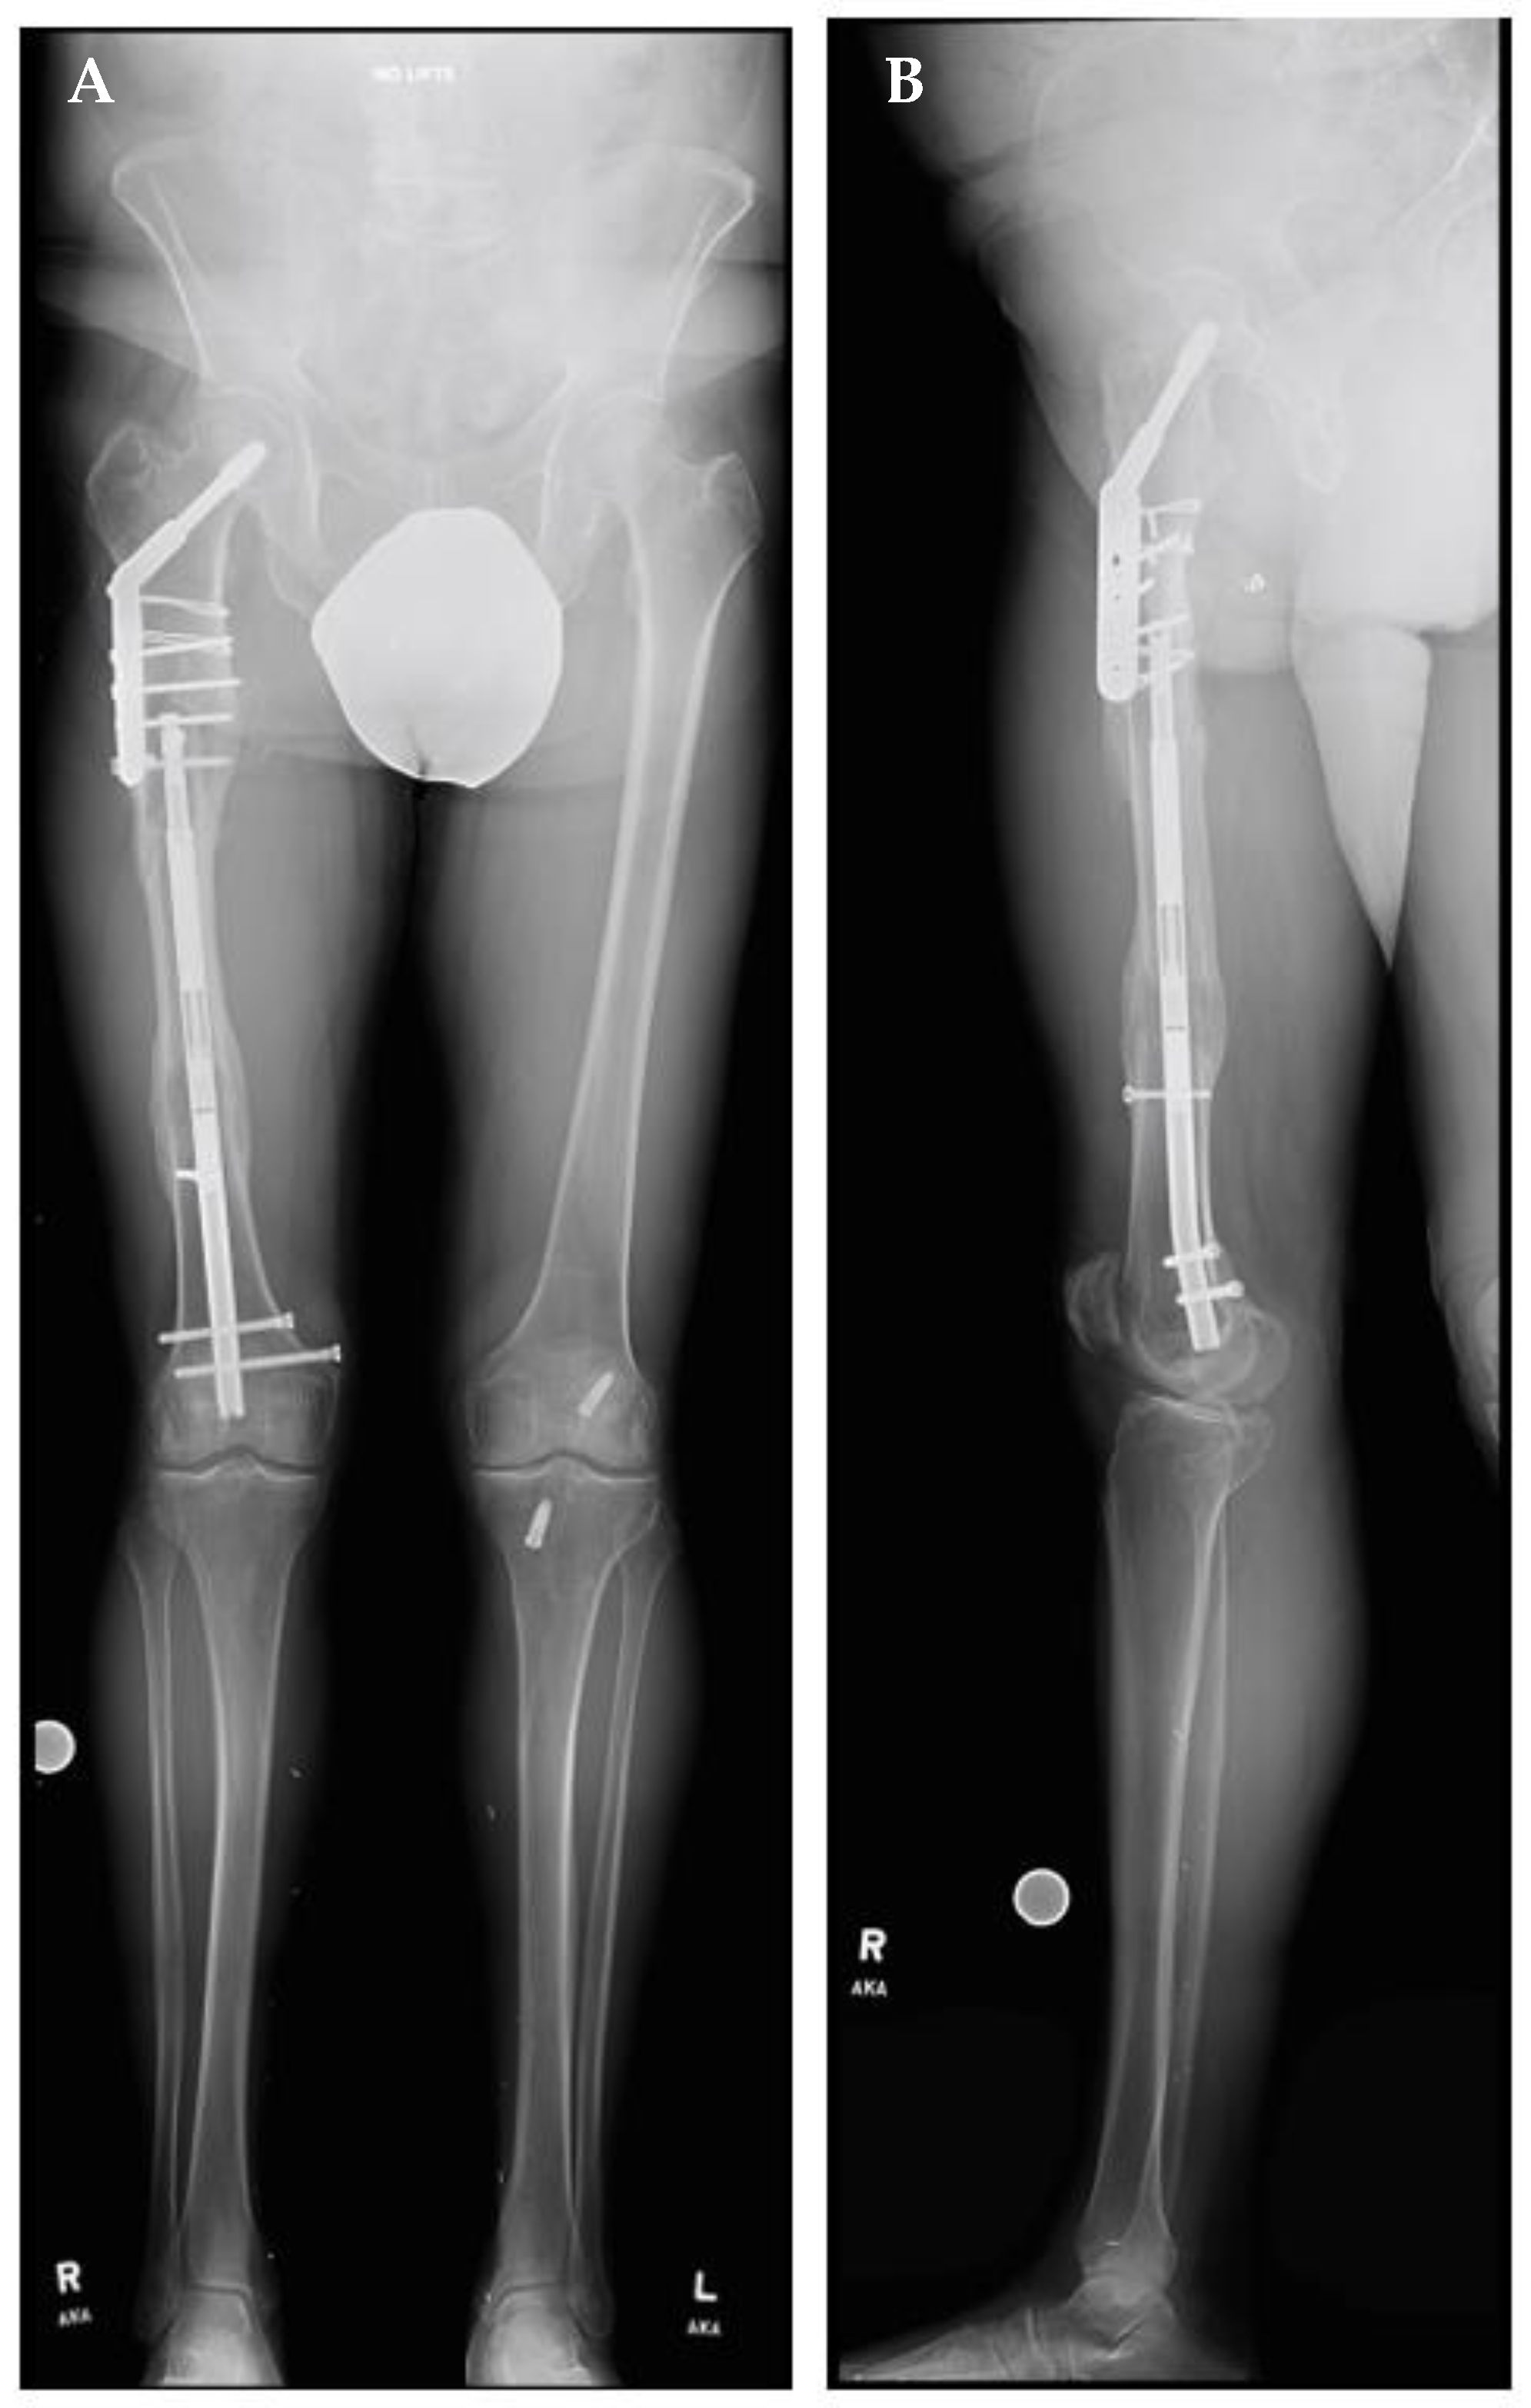

A right femoral osteoplasty was performed and a Precice MILN was inserted using the methods described above (Figure 2). The patient began lengthening as instructed on postoperative day five. He attended physical therapy and took vitamin D and calcium supplementation, as well as oxycodone as needed for pain management. Initial ROM of the knee joint was restricted from 0–50°, but full range was regained two months after surgery. He finished distraction 46 days after surgery (Figure 3). The patient completed consolidation 152 days after surgery and experienced no complications. At his latest follow-up appointment, his long leg films (Figure 4) demonstrated complete healing, remodeling, and equal limb length. The patient has returned to his active lifestyle, including skiing, and reported that he felt better on his bike and skis.

Figure 2.

Post-traumatic femoral lengthening in a 71-year-old male patient, shown here postoperatively. (A) Anteroposterior and (B) lateral of the right femur after osteoplasty and the insertion of the Precice MILN. Gray dots on the bottom represent X-ray calibration spheres.